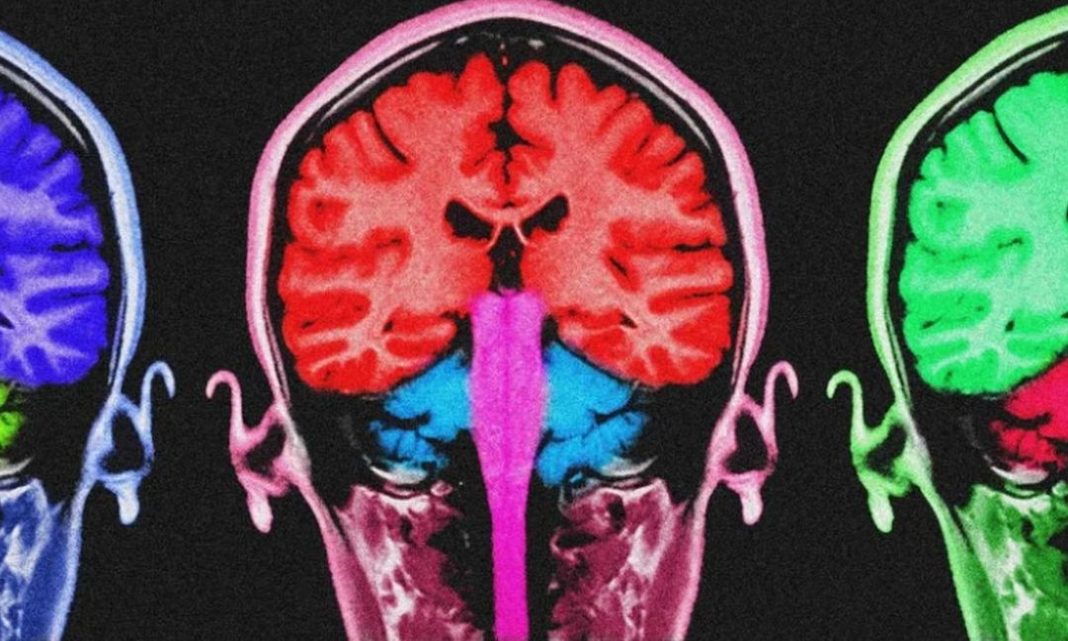

Σίγουρα, το σθένος μπορεί να σε βοηθήσει να προχωρήσεις. Όμως, μια νέα μελέτη διαπίστωσε πως αν βασίζεσαι αποκλειστικά σε αυτό για να ξεπερνάς τις δυσκολίες και δεν μαθαίνεις άλλους τρόπους να φροντίζεις τον εαυτό σου, μπορεί τελικά να προκαλέσεις ζημιά στον εγκέφαλό σου.

Περισσότερο σθένος, περισσότερη ζημιά στον εγκέφαλο;

Το συνεχές άγχος είναι καταστροφικό για το σώμα – αλλά είναι εξίσου επιβλαβές και για τον εγκέφαλο. «Η συνεχής έκθεση σε στρες μπορεί να υπερλειτουργήσει ορισμένα μέρη του εγκεφάλου», λέει η Εσιάκα. «Αυτή η ζημιά μπορεί να συσσωρευτεί και να κάνει πιο δύσκολη τη μάθηση νέων πραγμάτων, την απομνημόνευση και τη διατήρηση της πνευματικής διαύγειας όσο μεγαλώνουμε».

«Με τον καιρό, αυτή η συνεχής καταπόνηση μπορεί να οδηγήσει σε υπέρταση, εγκεφαλικά επεισόδια και κατάθλιψη – όλα τους έχουν συνδεθεί με γνωστική εξασθένηση», γράφει η Εσιάκα.